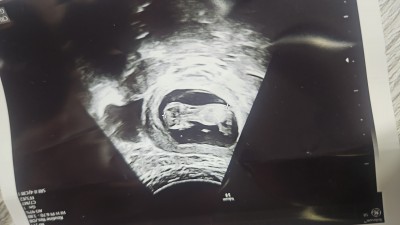

Kızlar merhaba 11 haftalik hamileyim. Kontrolde doktor kararsız kaldım önce kız gibi geldi ama şuan da erkeğe benzettim dedi. Bir daha bakiyim dedim erkek gibi görünüyor 1 ay sonra gel netleşir dedi. Fotoğraf yüklüyorum sizce ?